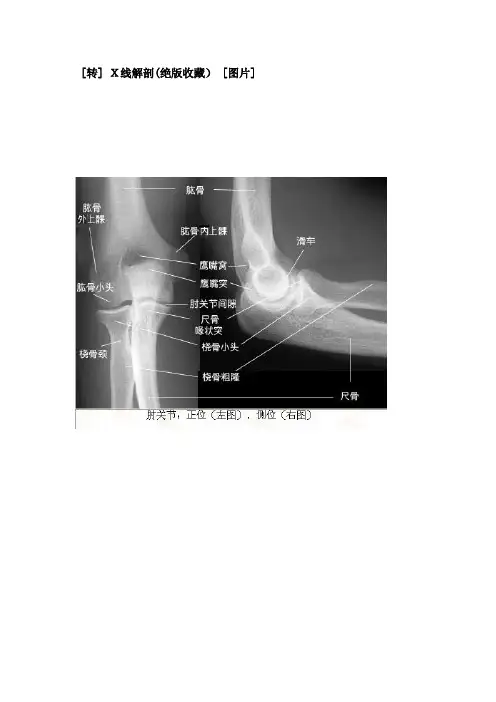

肘关节

正位(左图),侧位(右图)平片